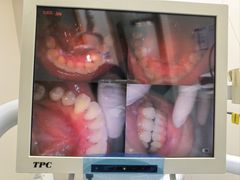

• 深圳尔睦丽沙口腔门诊部(丽沙花都店)

• -深圳尔睦丽沙口腔门诊部(丽沙花都店)